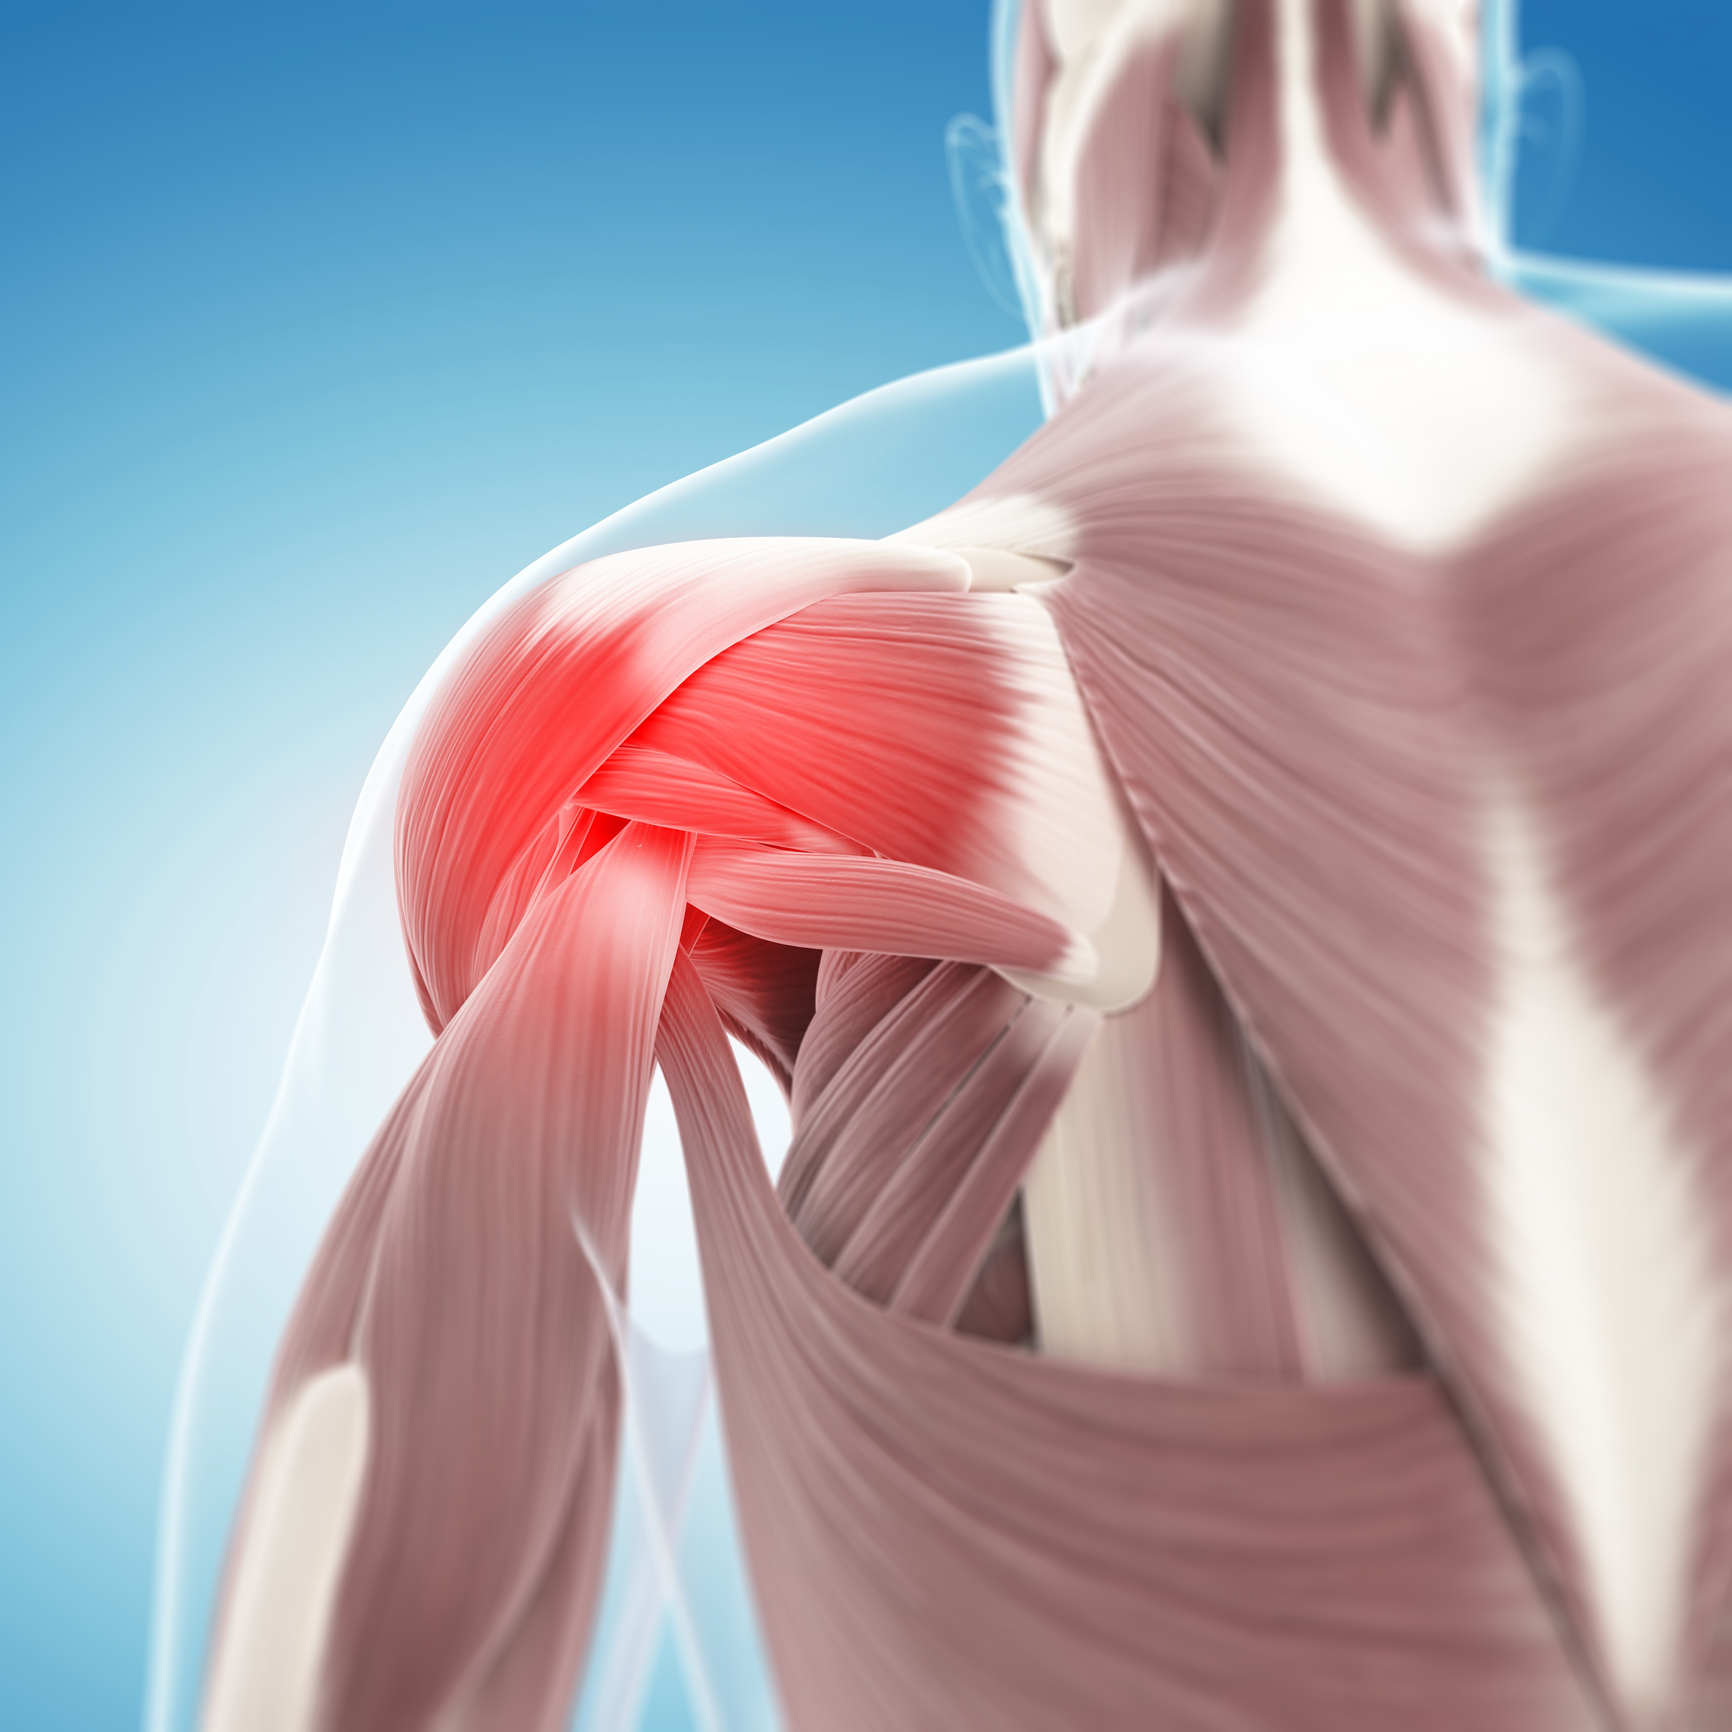

Фотографии поддельтовидной мышцы плечевого сустава